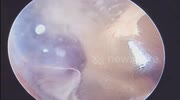

Unbelievable! Tumor Behind Eardrum Reacts to Man's Voice in Vietnam

Video captured the moment of Strange tumor behind eardrum pulsates with man's words in Ha Noi, Vietnam.

The man went to the hospital and said that recently he felt like he heard a drum sound in his ear. After examination, the doctor unexpectedly discovered a small tumor hidden deep behind the man's eardrum. Every time the man opened his mouth to speak. The tumor would move according to the man's words. The doctor said that this was a rare case during the doctor's examination. What was special was that the tumor was located behind the eardrum, so removing the tumor required many steps of examination.